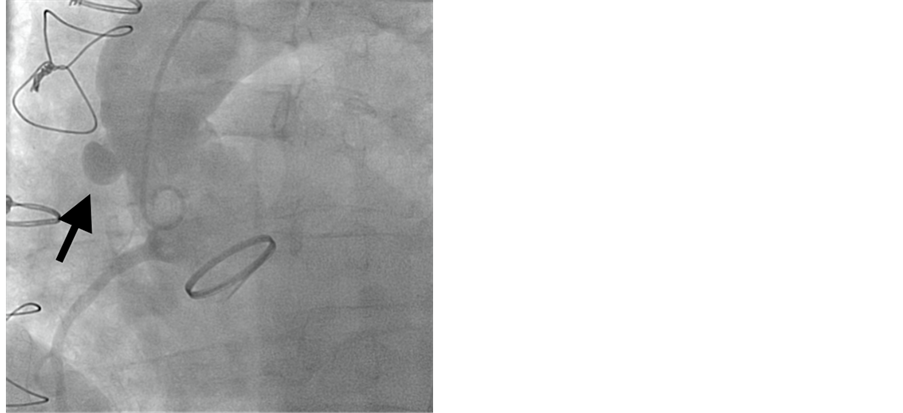

Eight months following the surgery, he presented to the emergency room of a local community hospital with chest pain radiating to his both arms of 2 hours of duration. 12 lead EKG revealed lateral ST elevations with marked ST depression. The patient was already on oral anticoagulation with an INR of 2.8. Heparin 4000 units was given intravenously. He was taken to the cardiac catheterization laboratory where he developed hypotension and multiple episodes of ventricular fibrillation requiring defibrillation, intubation and intravenous amiodarone. Bilateral femoral arterial access was obtained and 6F sheaths were placed. A 40 cc intra-aortic balloon pump (Sensation plus, Maquet, Germany) was inserted. After a brief discussion with the cardiothoracic surgical team at the tertiary hospital, decision was made to perform primary PCI at the local hospital in view of the patient’s critical condition and the inability to transfer him in a timely fashion. Aortic angiography revealed total occlusion of the left limb of Cabrol graft with TIMI 0 flow and a patent right limb of the graft with TIMI-3 flow (Figure 1).

Figure 1. Aortogram in LAO view showing occlusion of the Cabrol stump (arrow).